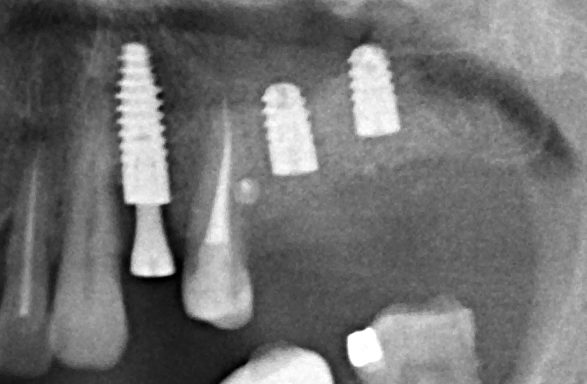

Для этого мы сделали КЛКТ:

И КЛКТ показала нам, что с имплантатами и окружающей костью всё зашибись. Через 12 лет после операции, отсутствия наблюдения, пофигизма в замене временных коронок! Нужны ли тебе еще какие-нибудь доводы в пользу долгосрочной эффективности метода?

Серия контрольных снимков на этапах: